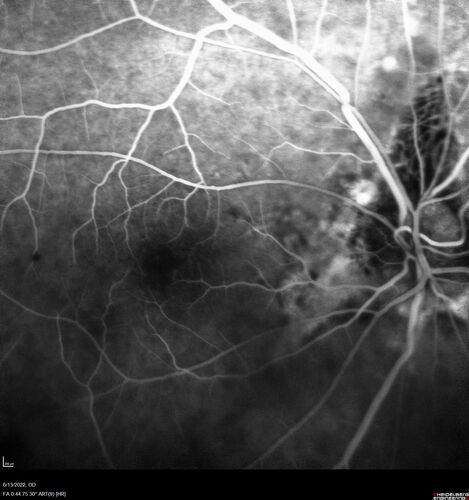

Optic nerve (disc) drusen and choroidal neovascular membrane

85 year old man - The left eye has had poor vision for 7-8 years.  The right eye is OK.  He was in for a checkup and his ophthalmologist noticed a problem and asked him to see retina doctor.

VA OD: Dcc20/25-2 OS: DccCF 1ft

Patient's right eye was treated with Avastin and was dry with one shot.